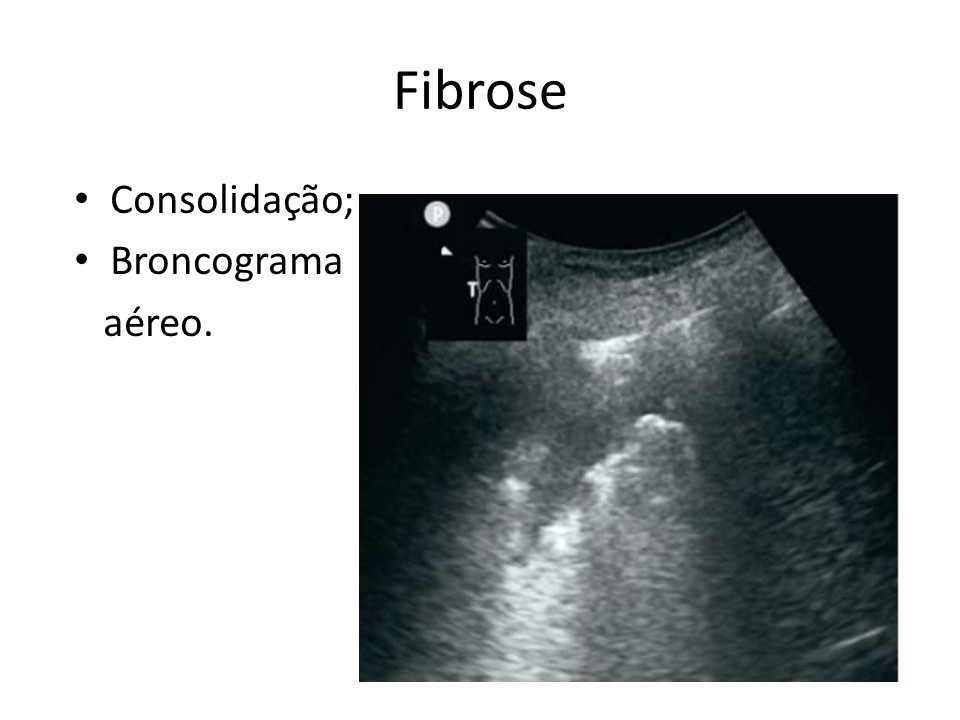

Inicio Imagem de ultrassom mostra marcas em pulmão com fibrose causada pelo coronavírus (Divulgação)